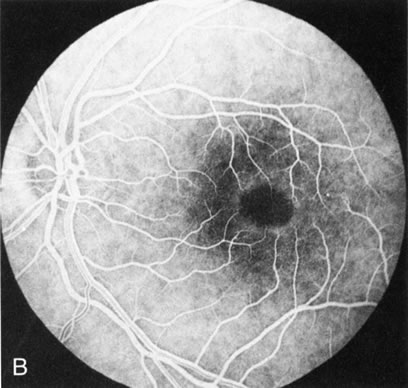

Dye leakage in RP may occur from the retinal vessels or at the level of the retinal pigment epithelium (Fig. 1B).2–4 The leakage may be seen in the macula and posterior pole, along the vascular arcades in the distribution of the radial peripapillary capillaries, and in the periphery (where an exudative vasculopathy resembling Coats' disease is suggested).

Of more clinical importance is the role of FA in the diagnosis and treatment of cystoid macular edema (CME) (Fig. 1C and D). Stereoscopic FA indicates that the leakage, which may be diffuse or have the typical petaloid stellate appearance of CME, can come from the perifoveal retinal capillaries, from the choroid through the RPE, or from a combination of both sources.4 With the recent suggestion that CME in RP may be successfully treated with acetazolamide,5, 6 FA is thus important to document the diagnosis of CME, establish the origin(s) of leakage, and follow patients during and after therapy.